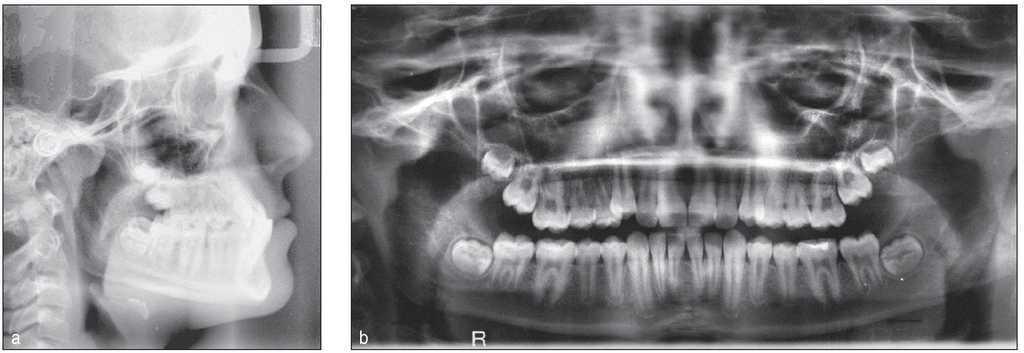

Este paciente presentaba una clase I dental con mordida cubierta. También existían una discrepancia de Bolton y espacios en el sector anterosuperior. Los incisivos centrales superiores estaban retroinclinados1. La arcada inferior estaba bien formada salvo por la presencia de un apiñamiento en el sector anterior (figs. 15 a 18).

Figura 17. Inclinación marcada del sector anterosuperior, dientes 11 y 21 retroinclinados.

Figura 18. Apiñamiento en el sector anteroinferior.